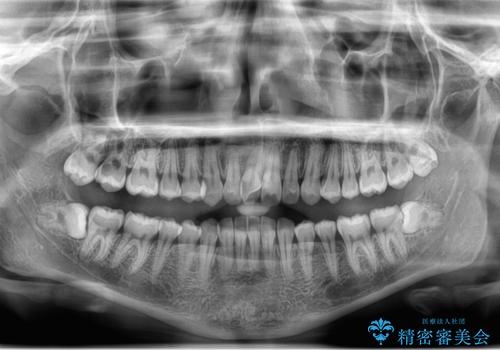

- 左上下親知らず抜きたいとの事で来院。

レントゲン、CTを撮影し安全を考慮して抜歯術を行いました。